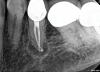

Fig 6. Identifiable inadequate NSRCT is associated with predictable RETX. Fig 6: Preoperative periapical radiograph showing AP, tooth No. 20. Fig 7. Postoperative periapical radiograph. Fig 8. Six-month follow-up periapical radiograph showing a significant decrease in size of the AP.

Figure 6